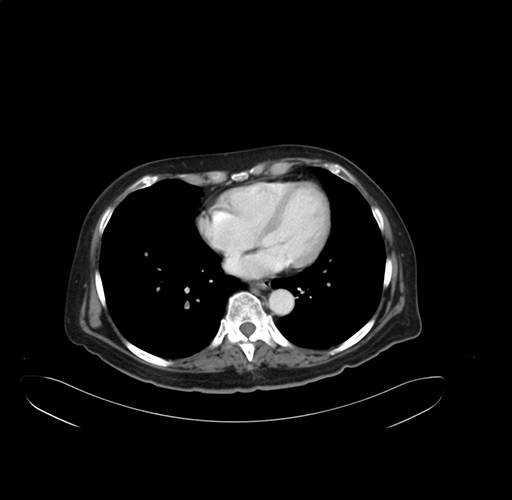

Pre-Chemo: Axial Venous

Axial Venous